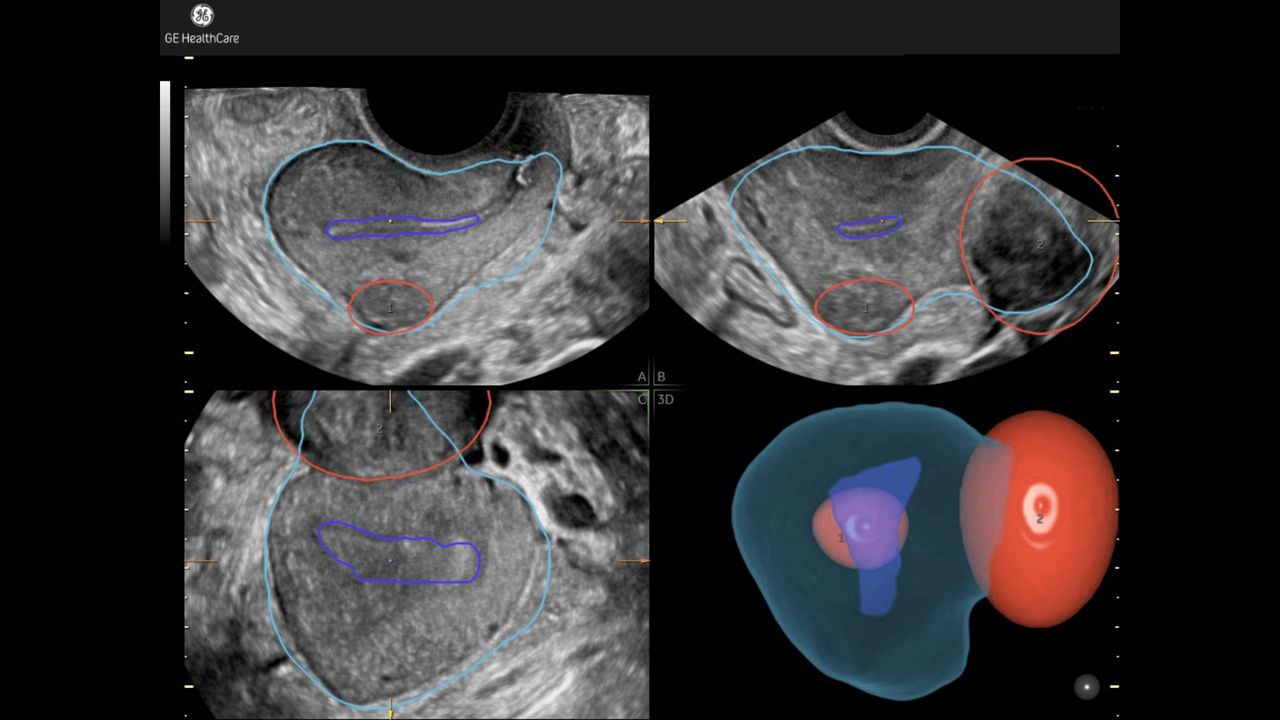

Fibroid Mapping

Uterine fibroid location & size highlighted in 3D.

Developed by: GE HealthCare - Voluson™

Fibroid-Mapping-Feature card Desktop